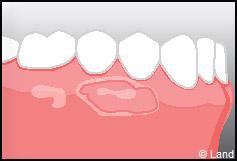

Les greffes de conjonctifs enfouis :

Destinées aux zones esthétiques, elles consistent à prélever la partie profonde du palais (site donneur).

Ce greffon est ensuite inséré sous la gencive au niveau de la récession (site receveur).